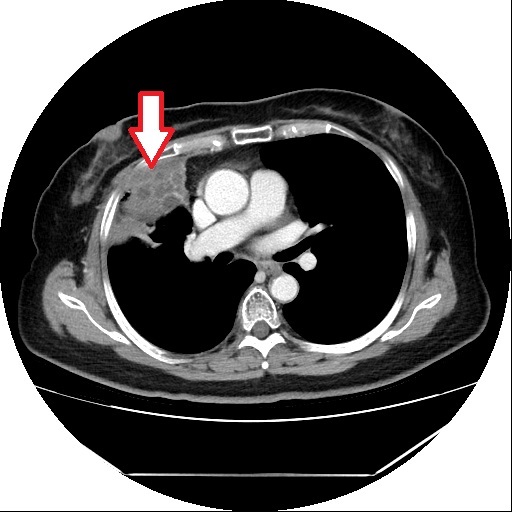

▲ 肺腺癌病灶位置。(圖/亞大醫院)

亞洲大學附屬醫院胸腔外科主治醫師周奇霈指出,王先生的腫瘤屬於早期肺癌,雖然腫瘤僅有2公分,但其形狀和位置顯示出高度的惡性可能性。即使在早期,肺癌也容易透過淋巴系統擴散,因此醫師建議進行手術切除腫瘤所在的肺葉,並清除多處縱膈與肺門的淋巴結,以確認是否已有轉移。